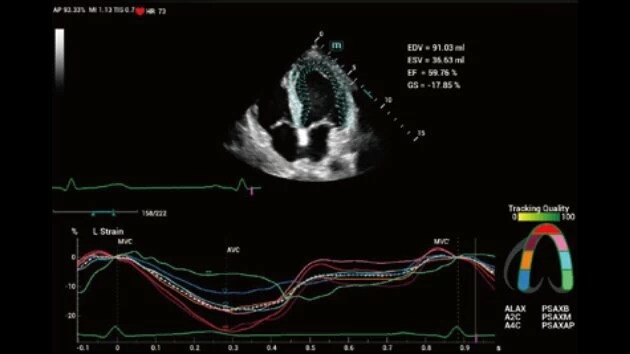

- Высокое разрешение изображений для точной диагностики

- Расширенный набор диагностических функций

- Широкий спектр клинических исследований

- Расширенные возможности визуализации различных органов и тканей